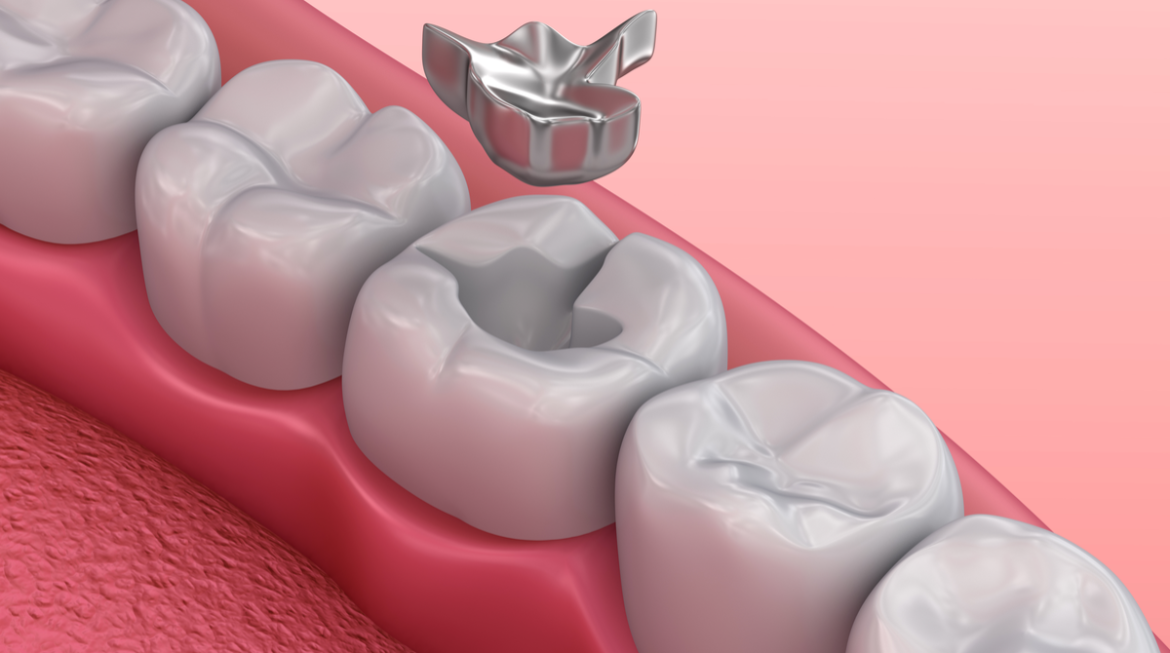

Can I Have My Dark Colored Fillings Replaced with Tooth Colored Fillings?

Have you ever looked at a picture of yourself mid-laugh and cringed at all the dark spots on your back teeth? If you’ve had any amount of dental work completed then this is likely a familiar scenario. In the past, the most effective and long-lasting fillings consisted of a dental amalgam (mixture) made from a combination of metals. The result was a filling that looked dark silver in color. This dark material got the job done but was not esthetically pleasing. Today, advances in technology have provided us with an alternative option to the dark fillings of the past. That …